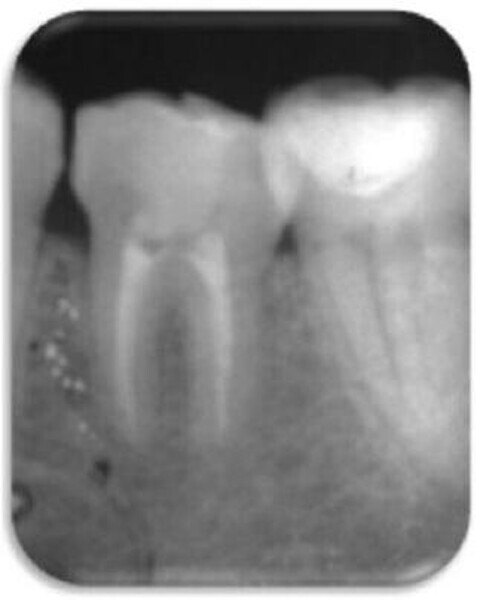

Leczenie endodontyczne autogennego przeszczepu zęba